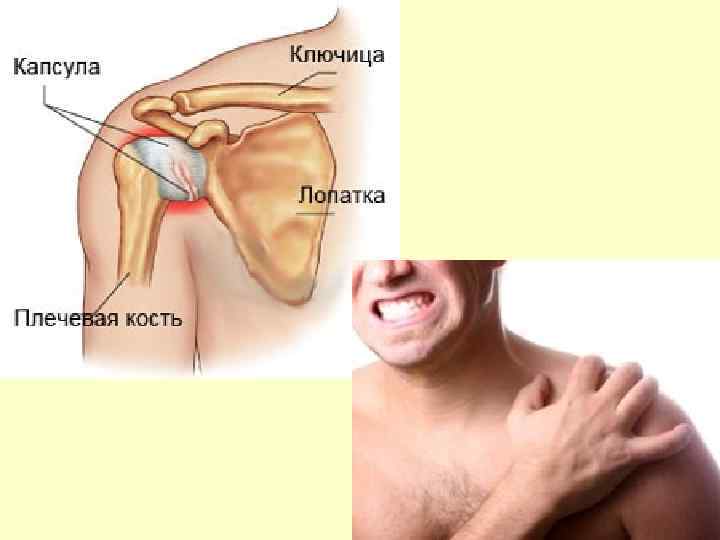

Плече-лопаточный периартроз • Заболевание возникает как результат длительного перенапряжения мышц плечевого пояса, вследствие резких, усиленных движений в плечевом суставе, что сопровождается постоянной травматизацией тканей вокруг сустава. • Наиболее часто данное заболевание наблюдается у тех рабочих, чья работа связана с длительным отведением и подниманием работающей руки, совершением поворотов плеча в большом объеме, причем чаще всего у женщин. Обращает на себя внимание односторонность проявления, в частности преобладание поражения правой верхней конечности, что является дополнительным доказательством влияния профессионального фактора на возникновение и развитие заболевания.

• При выполнении работы, сопровождающейся частыми боковыми отведениями и вращениями плеча в большом объеме, возникают условия длительной травматизации связочного и сухожильного участков плечевого сустава и суставной сумки. При этом возникают их дегенерация и дистрофия, т. е. “перерождение” клеток и тканей с нарушением их функциональной активности. • Процесс сопровождается развитием асептического немикробного воспаления околосуставных тканей с возможным последующим обезызвествлением тканей и сдавлением капсулы плечевого сустава. • Термин “периартрит плечевого сустава” представляет собой собирательное понятие, так как объединяет целую группу заболеваний в области плечевого сустава. Каждая патология различается по топографии и особенностям клинической картины, но в целом они дают настолько сходную клинику, что объединяются под общим названием.